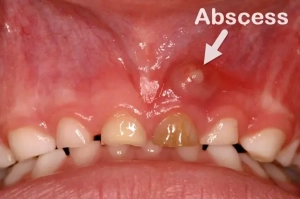

آبسه ایجاد شده روی لثه ها با نام التهاب لثه نيز شناخته می شود. آبسه لثه به صورت برجستگی های متورم روی سطح لثه ظاهر می شود. علت اصلی التهاب لثه، باکتری ها هستند كه اغلب از پلاک، ذرات مواد غذایی یا پوسیدگی دندان ناشي مي شوند که منجر به عفونت در زیر لثه می شوند. در برخي موارد نادر، التهاب لثه مي تواند نشانه سرطان دهان باشد.

آیا تا به حال دچار درد ناگهانی و تیرکشنده ای در لثه خود شده اید؟ یا شاید متوجه برآمدگی کوچکی روی لثه تان شده اید که با فشار دادن، مایع بدبویی از آن خارج می شود؟ اگر پاسخ شما مثبت است، ممکن است با آبسه لثه روبرو باشید؛ یک بیماری جدی که بی توجهی به آن می تواند مانند آتشی زیر خاکستر، سلامتی دندان ها و حتی استخوان فک را تهدید کند.

در اغلب موارد آبسه لثه با درد همراه است اما در برخی موارد نادر آبسه لثه دردناک نیست. معمولاً درد اولین نشانه وجود آبسه در لثه های شما است. پس از احساس درد، آن قسمت را با زبان خود بررسی کنید یا با استفاده از یک آینه داخل دهان خود را مشاهده کرده و به دنبال برآمدگی در لثه خود باشید.

آبسه لثه را مانند یک بادکنک پنهان شده تصور کنید که در بافت لثه پر از باکتری و چرک است. این تجمع عفونت، زمانی رخ می دهد که بدن شما در حال مقابله با هجوم باکتری هایی است که به عمق لثه یا ریشه دندان نفوذ کرده اند. اگر به موقع درمان نشود، ممکن است این “بادکنک عفونی” بترکد و عفونت را به دیگر نواحی دهان یا حتی به بدن گسترش دهد.

علائم آبسه لثه می تواند شامل موارد زیر باشد:

- بوی بد دهان

- خونریزی

- ترشح چرک

- گوش درد

- تورم لثه ها

- حساسیت به گرما یا سرما

- حالت تهوع

- تب بالا

- تحلیل رفتن تدریجی لثه